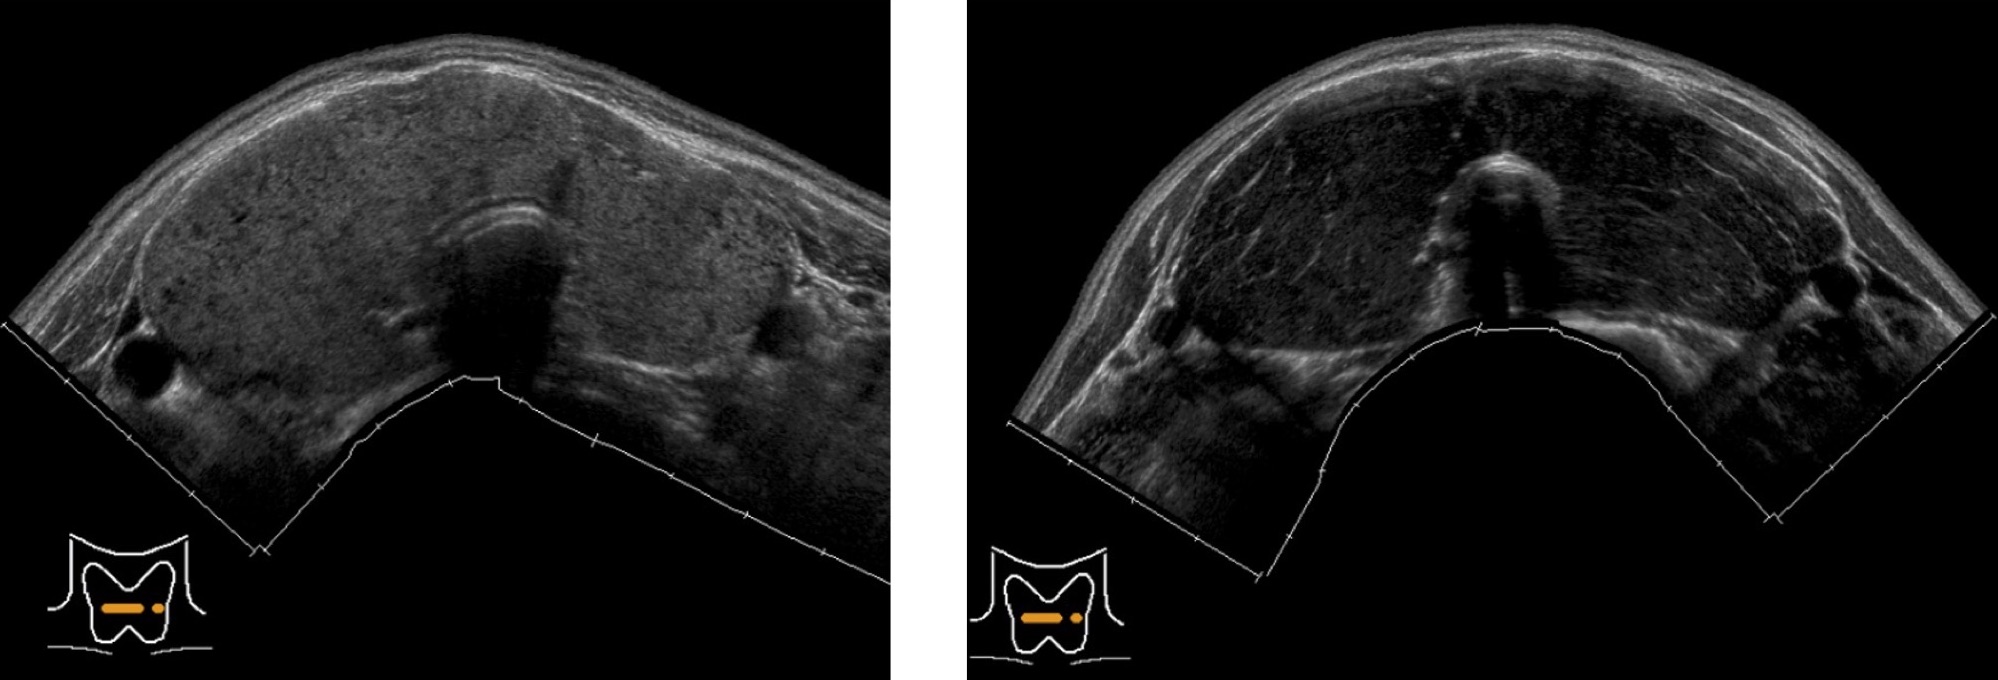

バセドウ病

甲状腺全体が腫れて大きくなり、血流が多くなります。

※軽症の場合は正常な甲状腺とほとんど変わらない場合もあります。

無痛性甲状腺炎

血液検査ではバセドウ病と同様に甲状腺ホルモンの値が高くなりますが、超音波画像ではバセドウ病と比べて血流が少ないのが特徴です。